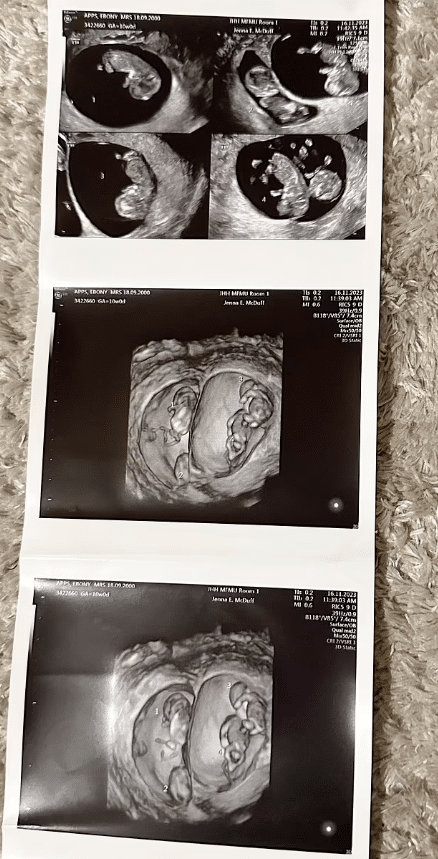

The attending doctor, breaking the news, revealed that they were not only expecting quadruplets but two sets of identical twins, which is rare even in multiple pregnancies.

The expecting mother’s condition, carrying two sets of identical twins, was described by the doctor as exceptionally rare.

“Our doctor told us that quadruplet pregnancies are around one in 700,000, and being pregnant with two sets of identical twins is even more rare.

“A nurse said that in her 30 years of experience, she has never seen this happen, Ebony said.

According to CNN, the likelihood of such a pregnancy is approximately one in 70 million.